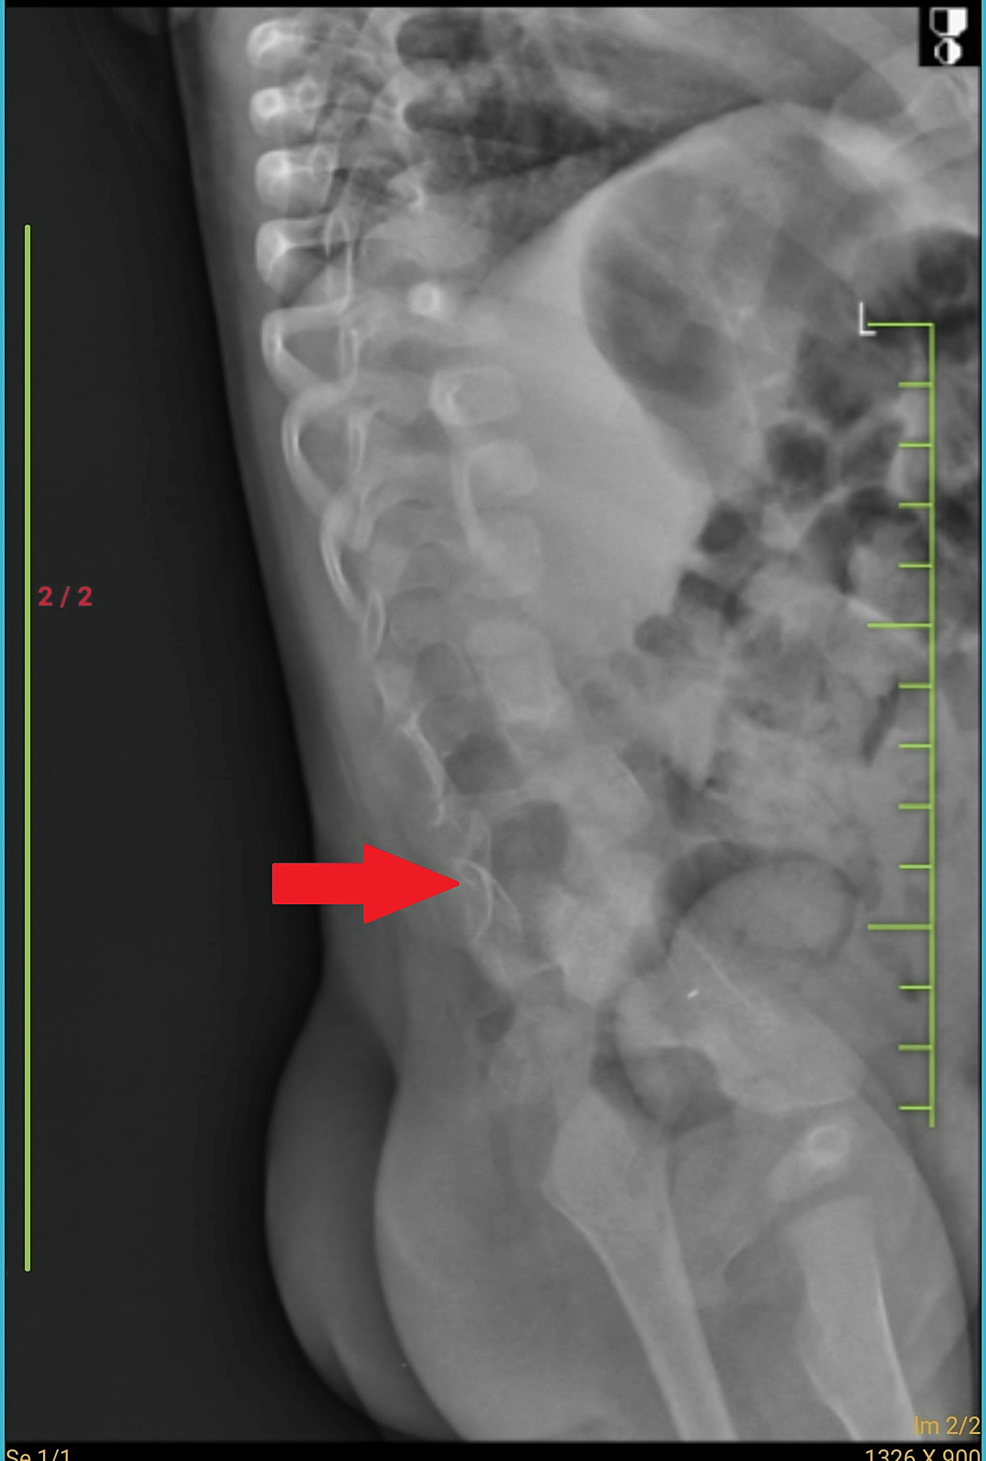

Butterfly vertebra Image

Butterfly vertebra Is a type of vertebral anomaly and results from the Butterfly Vertebrae Web the butterfly vertebra is a type of vertebral anomaly that results from the failure of fusion of the lateral halves of the vertebral. Web a butterfly vertebra is a vertebra with a midline sagittal cleft due to failure of fusion of the lateral halves of the. Web a butterfly vertebra (bv) is a rare congenital anomaly resulting from a. Butterfly Vertebrae.

Butterfly vertebrae seen in the thoracic region in children with Butterfly Vertebrae Web this article summarizes the demographics, clinical presentations, and conditions associated with butterfly vertebrae, a rare. Web this study is the largest collection of butterfly vertebrae cases to date. Web a butterfly vertebra is a vertebra with a midline sagittal cleft due to failure of fusion of the lateral halves of the. Web a butterfly vertebra (bv) is a rare. Butterfly Vertebrae.